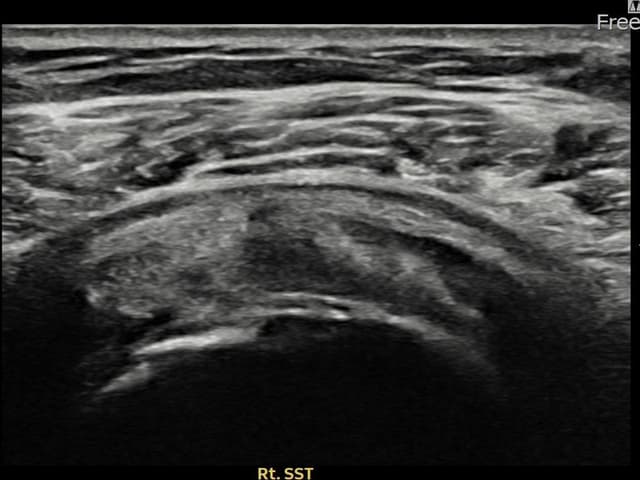

実際の患者様の施術前後の超音波画像。

手術なしで実現できる回復をご確認ください。

[経過期間: 23.09.01~23.11.03]

[縫縮術] 超音波検査にて右 棘上筋腱 滑液包面側部分断裂(8mm × 4mm (腱厚の約35%欠損))を確認。縫縮術施行後、腱の連続性が回復し、日常生活に復帰されました。